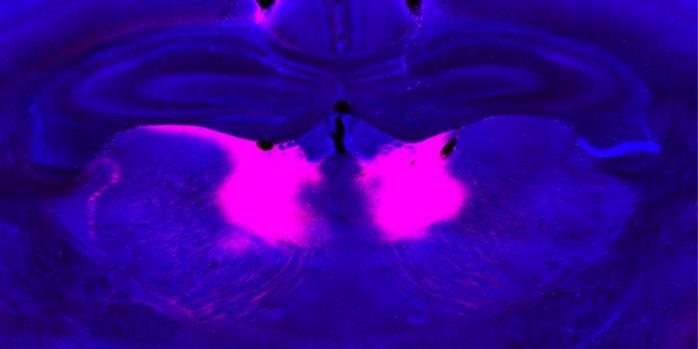

За допомогою функціональної ультразвукової візуалізації та електроенцефалографії вчені виявили, що областю мозку, на яку мутація grin2a вплинула найбільше, є медіодоральний таламус. Ця частина мозку з'єднується з префронтальною корою, утворюючи таламокортикальний контур, який відповідає за регулювання когнітивних функцій, таких як виконавчий контроль та прийняття рішень.

Вчені виявили, що нейронна активність у медіодоральному таламусі, судячи з усього, відстежує зміни цінності двох варіантів винагороди.